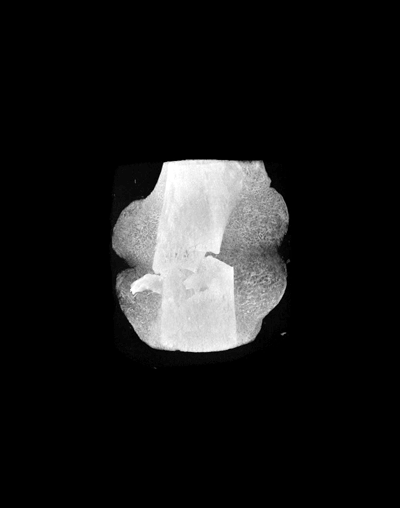

Micro-computed tomography (μCT) is a three-dimensional, X-ray-based imaging modality that can image tissues, organs and whole organisms as well as nonorganic structures with a spatial resolution as high as 6-10 μm. μCT systems provide rapid, quantitative, high-resolution and three-dimensional assessment of both microstructure and density. μCT is nondestructive and can scan ex-vivo samples as large as 75 cubic centimeters in several hours.

The Micro-Computed Tomography Imaging Core Facility at BU has one μCT scanner and one X-ray microscope. The μCT scanner is a Scanco μCT40 system which is density calibrated on a weekly basis to keep our scans accurate. The XRM is the Zeiss Xradia Versa 520. We have multiple software options that allow for the identification of sub-regions for image segmentation, registration, and quantitative analysis. Analyses can be performed on three-dimensional regions of interest to quantify porosity, thickness, and other features of the microstructure. Additionally, two-dimensional regions of interest can be analyzed to quantify bone area, bone area fraction, cross-section area, and moment of inertia. We have the ability to render and export images in a variety of file formats.